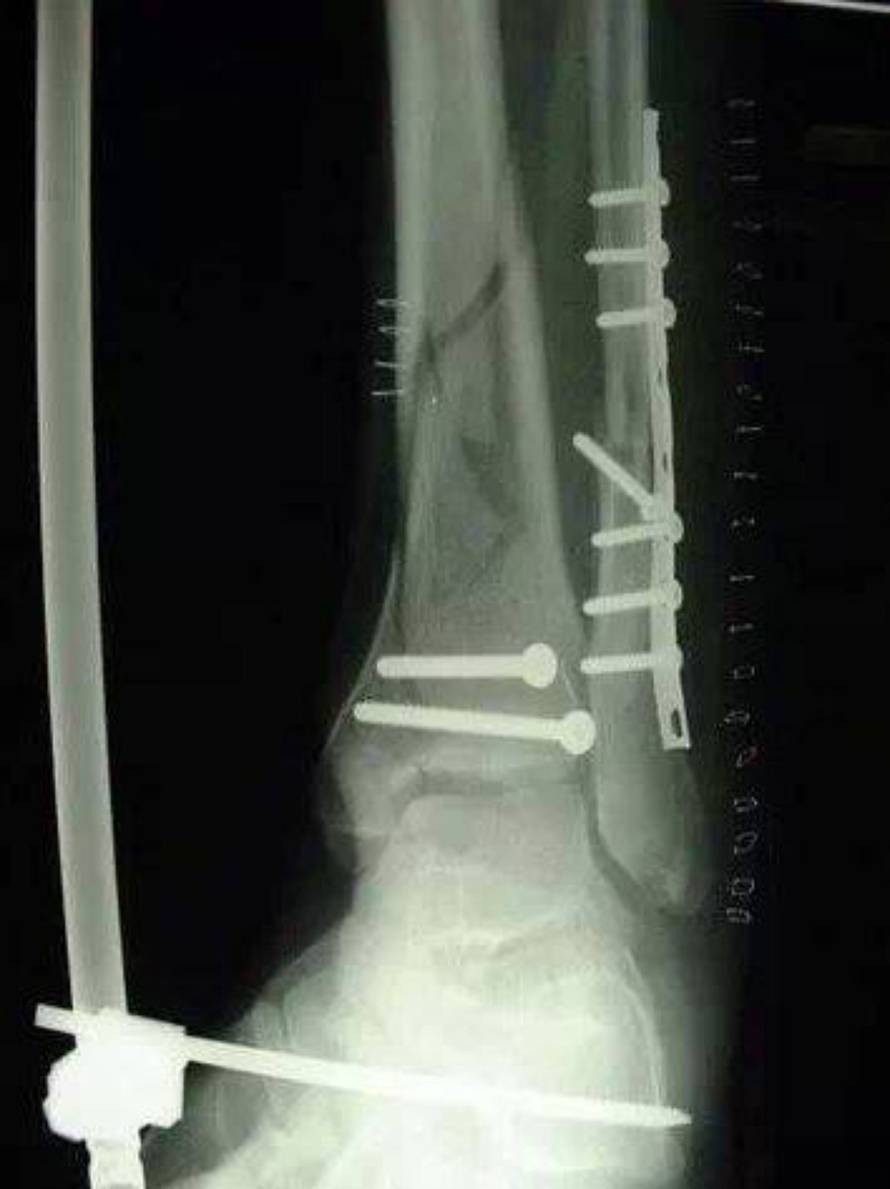

Anderson Silva doživio je težak prijelom potkoljenice u borbi za titulu prvaka UFC-a u srednjoj kategoriji protiv Chrisa Weidmana. Vjerojatno će objaviti kraj karijere...